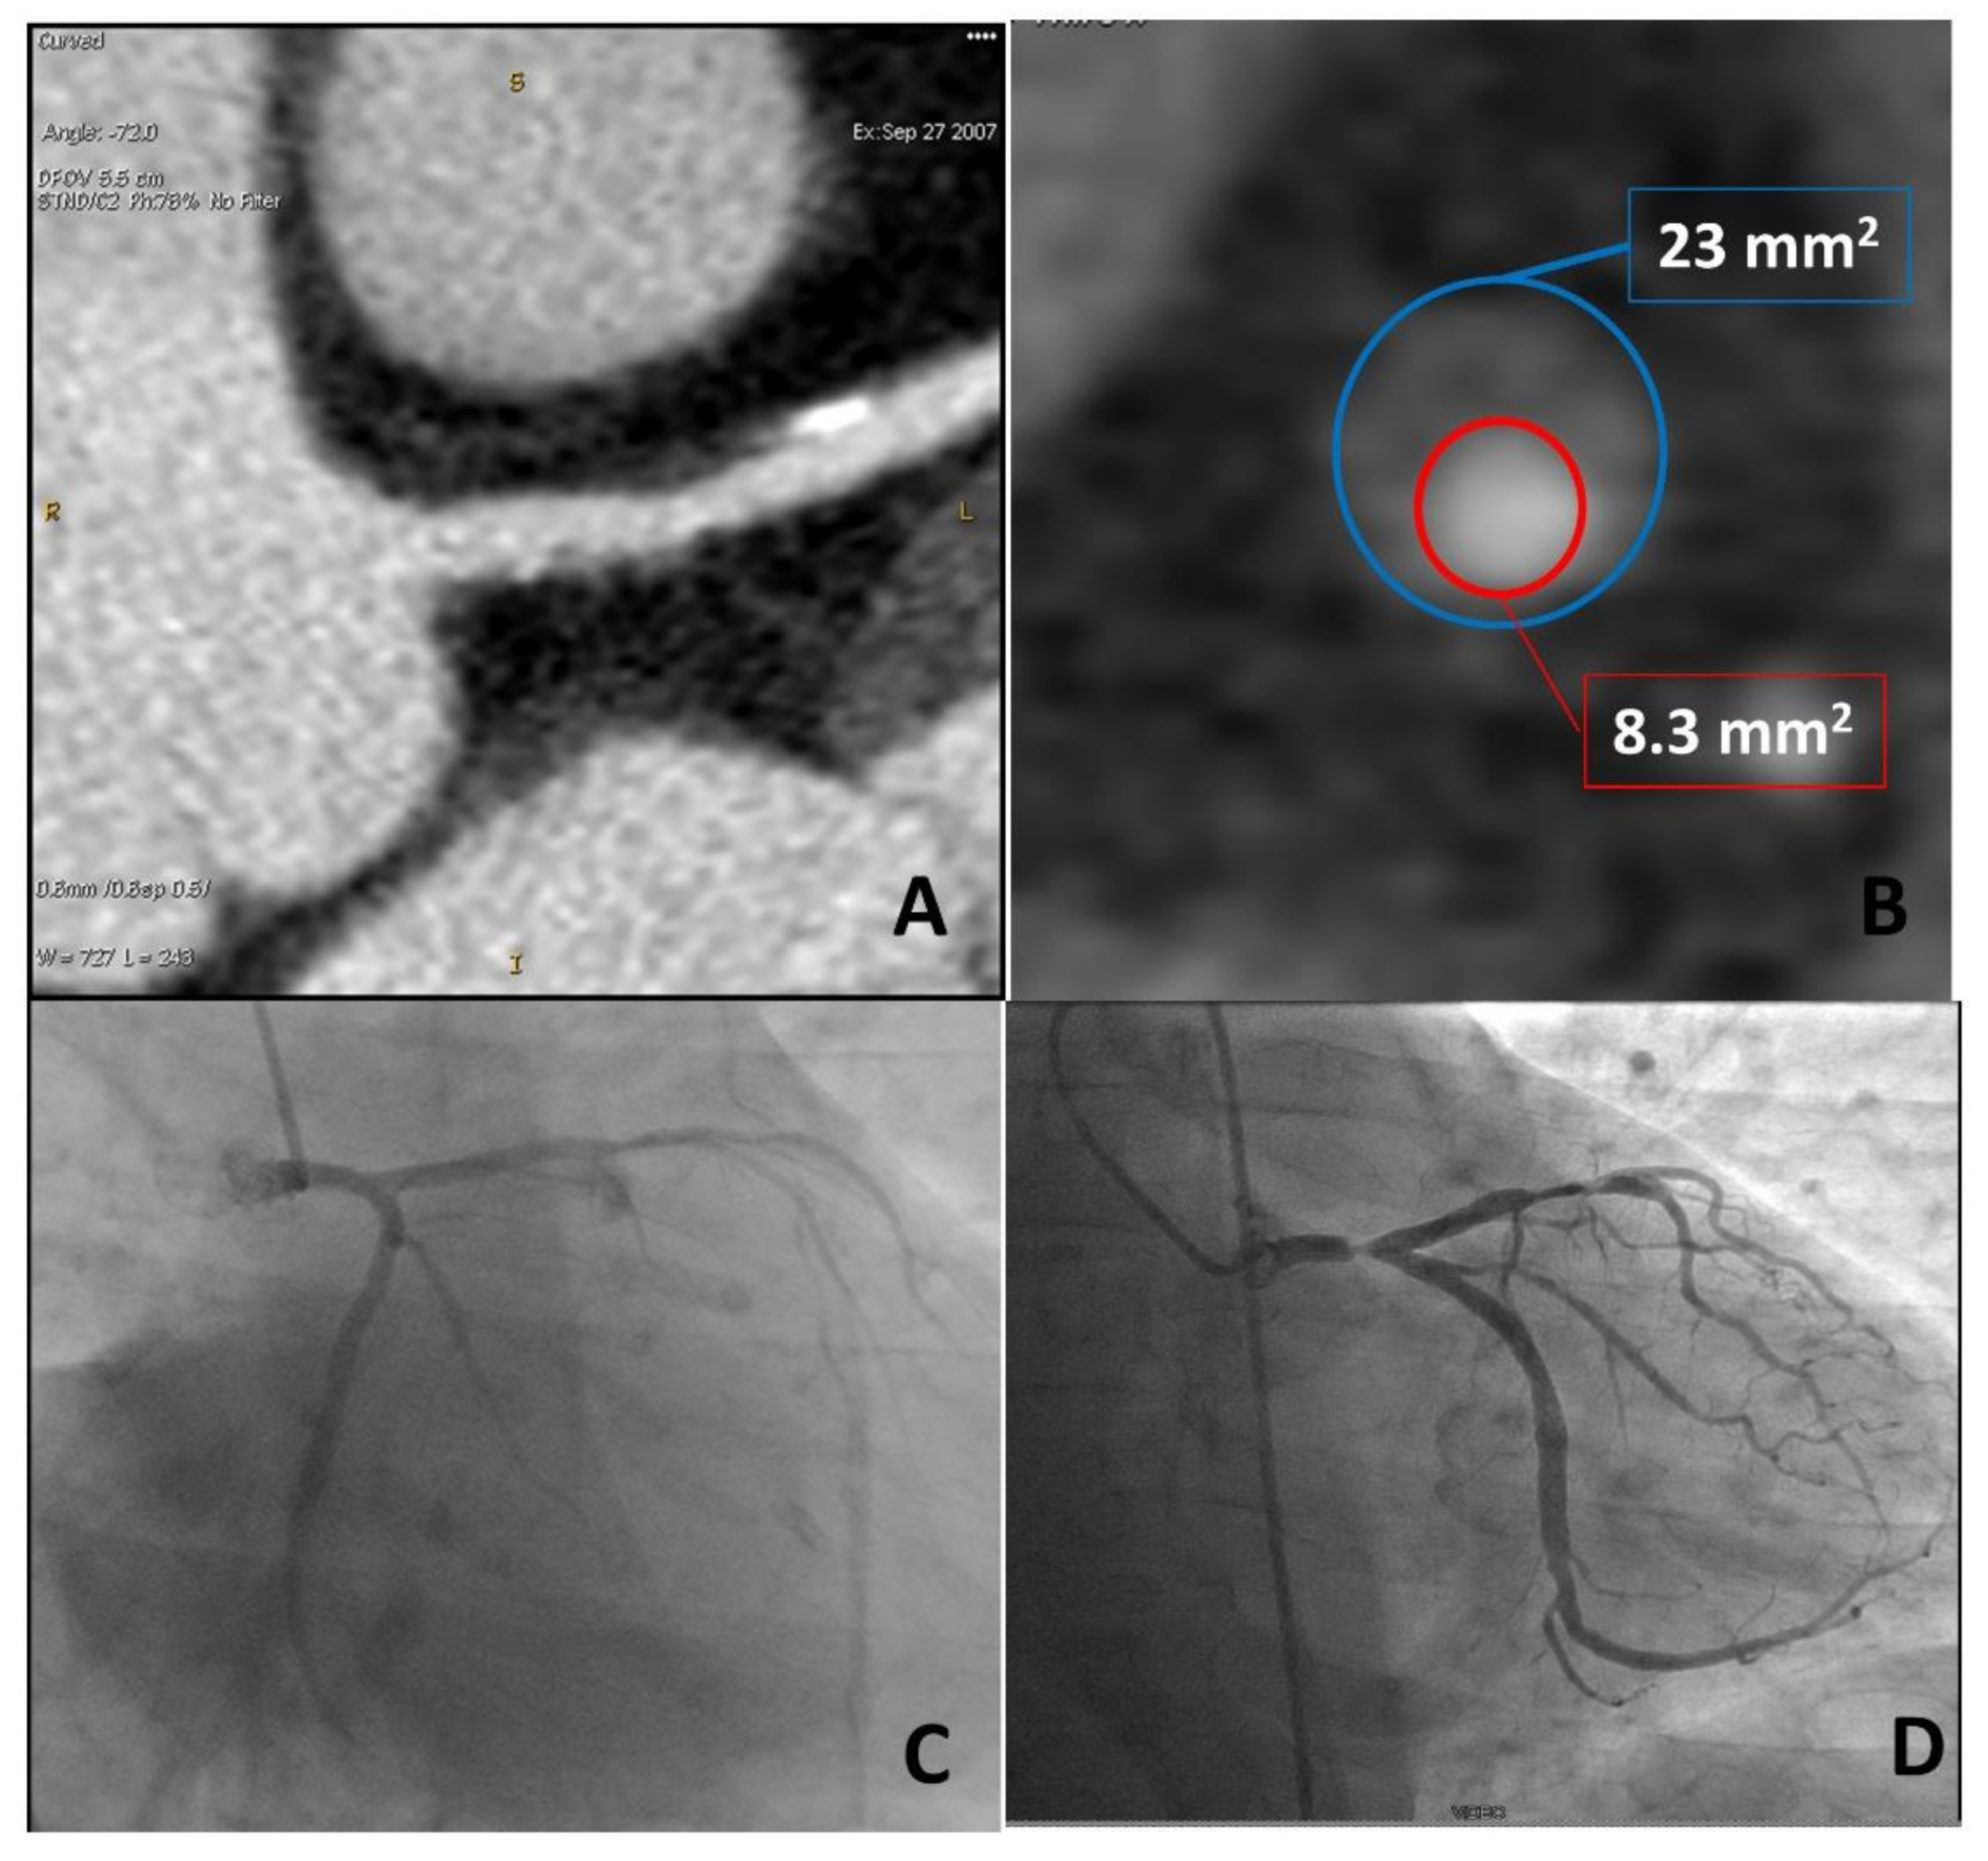

| Remodeling index (RI) | Ratio between lesion plaque area (red circle) and reference lumen area (blue circle). Positive remodeling is defined as RI > 1.1. | ![]() |

| Plaque burden (PB) | Derived by the following formula: (lesion plaque area (red circle)—lesion lumen area (blue circle))/lesion plaque area (red circle). | ![]() |